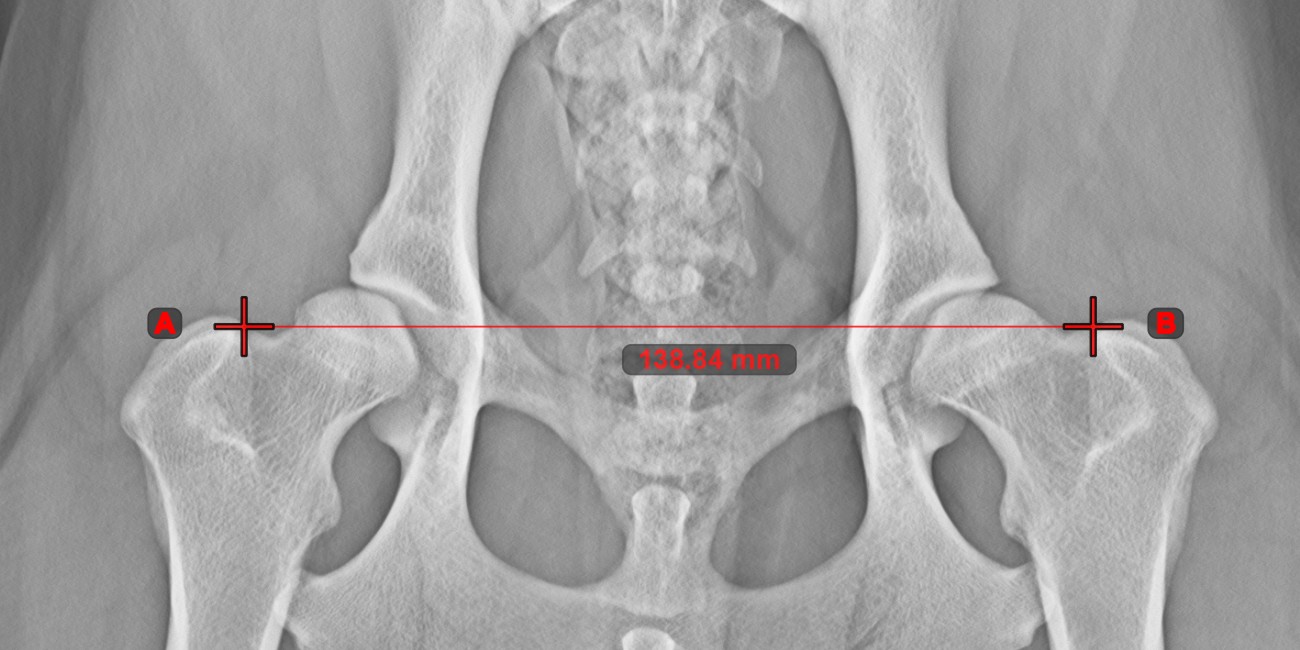

Line Measurement

Create a line measurement to calculate the distance between two points with high precision.

Select the Line Measurement tool and assign it to one of the available mouse buttons. Place the start and end points on the scene or select them from already existing points on the image. The distance between the two points will be automatically calculated by using the default calibration data, or the recalibrated data by the length calibration measurement.

Modify the start and end point by using the Select/Move Item tool. The distance between the two points will be automatically recalculated.

../_images/image164.jpg